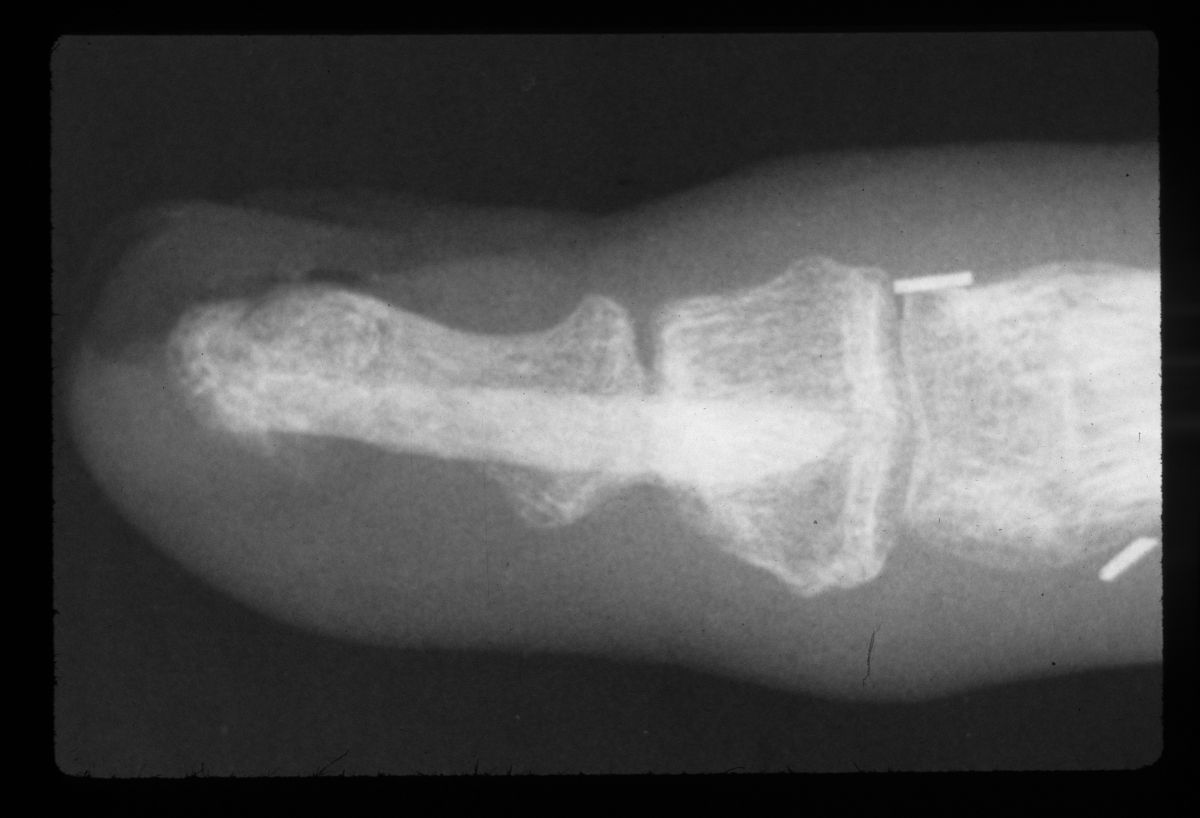

| Case 1. This patient presented with a progressive index finger nail deformity years after an open crush injury of that fingertip. |

| Xrays show loss of much of the distal half of the distal phalanx, with cortical disruption. |